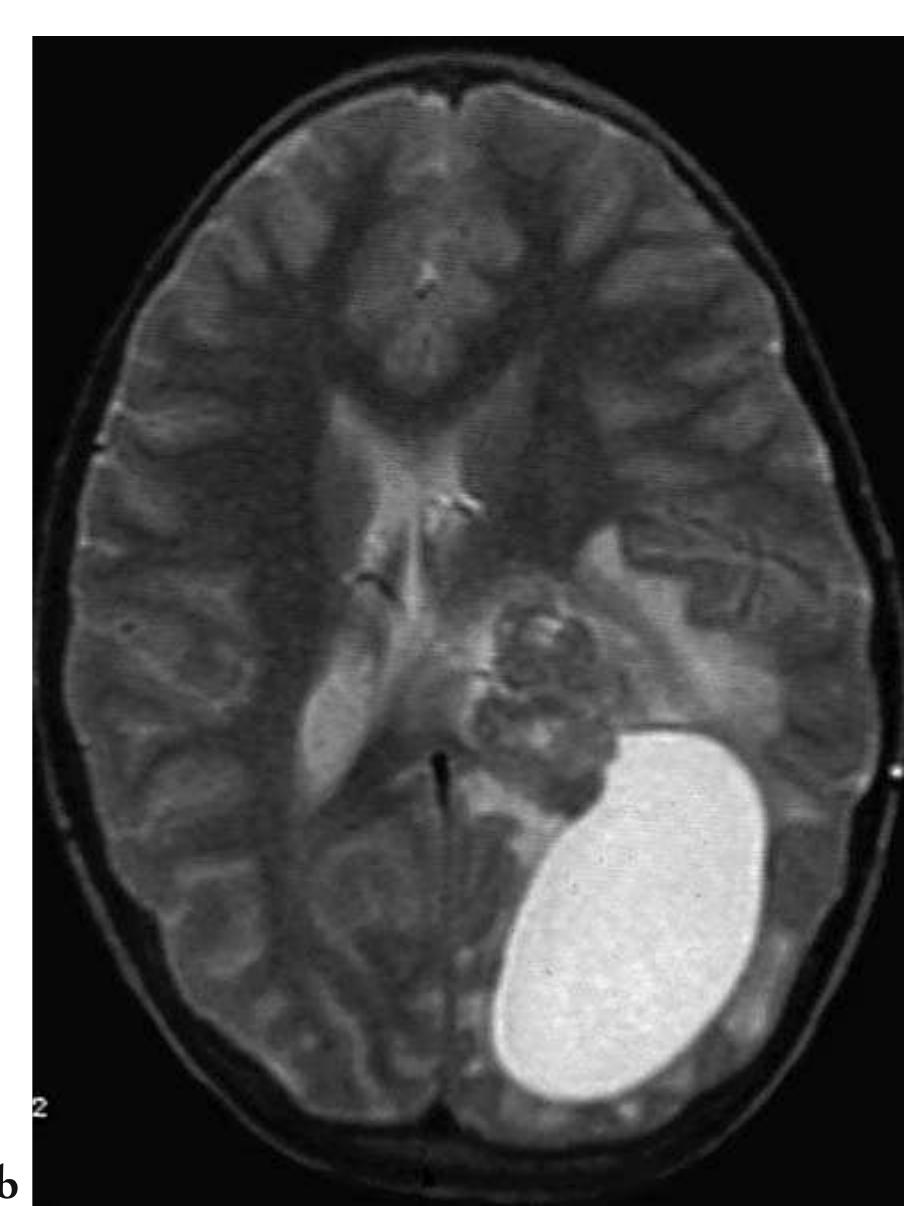

![Fig. 3.6 - Type II Arnold Chiari malformation with obstructive hydrocephalus The MRI examination demonstrates cerebellar tonsillar ectopia, fourth ventricular outlet obstruction and hy- drocephalus. In addition, there is right occipital encephaloma- lacic porencephalic cyst and cervicothoracic syringohydromyelia. [a) sagittal T1- weighted cranial MRI; b) sagittal T1-weighted cervical MRI; c) axial T2-weighted cranial MRI]. After a certain time, chronic inadequate flu- id reabsorption can produce an enlargement of the ventricles without an attendant increase in fluid pressure (normotensive hydrocephalus). In acute hydrocephalus, the CSF is reabsorbed vicariously by the minor resorption systems, firstly by the transependymal pathway, with the appearance of typical findings of hypodensity on CT and hyperintensity on T2-weighted MRI in the periventricular white matter (Fig. 3.8). This absorption pathway is more permeable than the normal one and permits the passage through the periventricular white matter of even large protein molecules.](https://figures.academia-assets.com/35610716/figure_209.jpg)